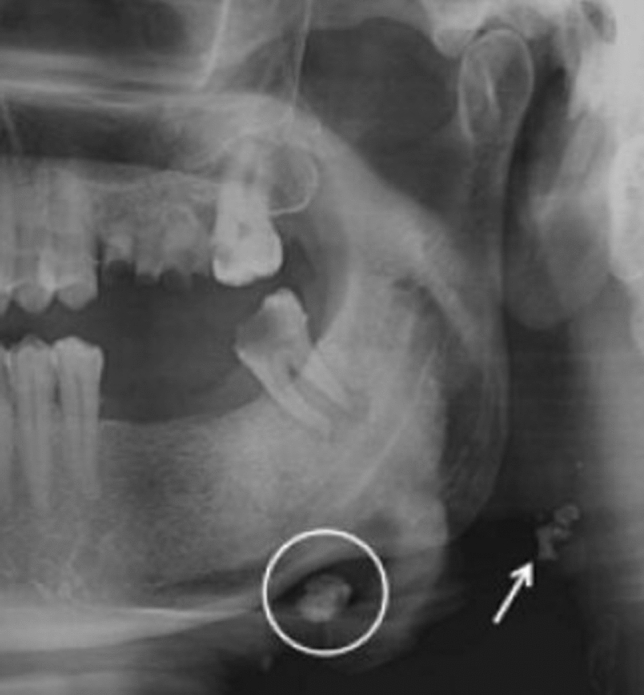

Fig. 1.

Bilateral carotid artery calcifications at the level of the third cervical vertebra. Superior horn of thyroid cartilage and triticeous cartilage observable at the level of the fourth cervical vertebra

a, b Bilateral carotid artery calcifications at the level of the third cervical vertebra. Superior horn of thyroid cartilage and triticeous cartilage observable at the level of the fourth cervical vertebra